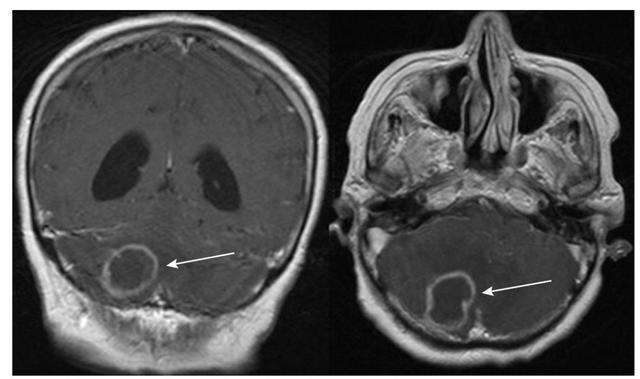

表格总结+实战读片:掌握急性小脑性共济失调的常见病因及诊断线索丨临床必备

图2 表现为急性共济失调的乳腺癌患者。诊断为副肿瘤性小脑变性;FLAIR可见小脑上蚓部明显高信号。